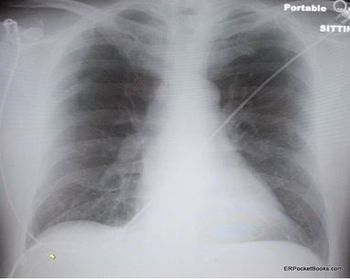

The symptoms have worsened over a 2-month period. Past medical history is unremarkable. Here, review the ED chest x-ray film and ECG. Do you see any clues to a diagnosis?

Two weeks after injury to the right chest wall and shoulder, the patient continues to have pain. He also reports numbness and tingling in his hands bilaterally. What do the ED images reveal?